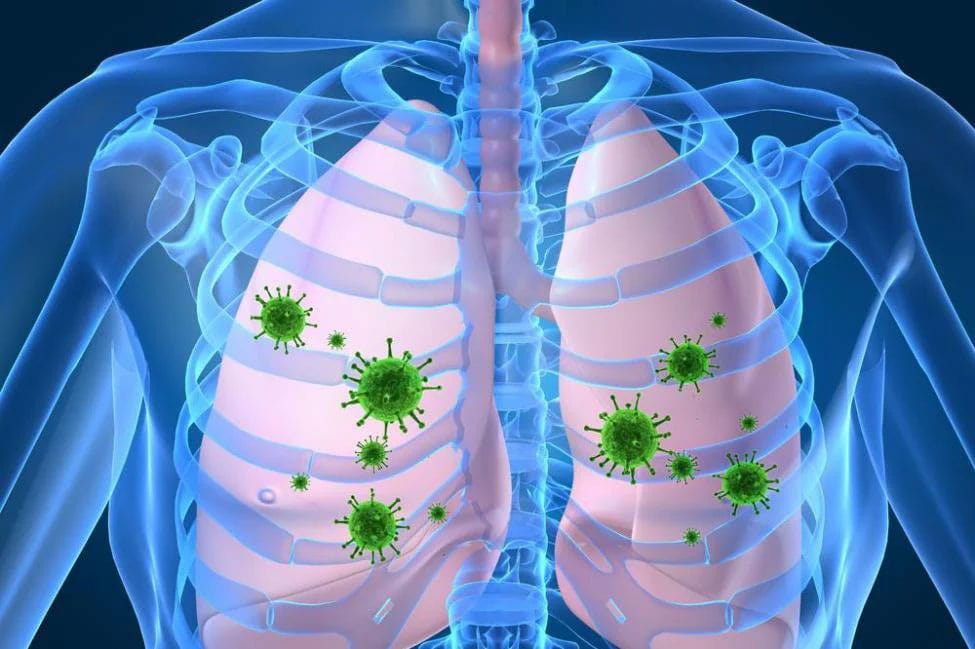

Những triệu chứng khi trẻ sơ sinh bị viêm phổi

SKĐS - Viêm phổi là bệnh hô hấp nguy hiểm, đặc biệt đối với trẻ sơ sinh. Tuy nhiên, nhiều trẻ nhập viện muộn, bị đe dọa đến tính mạng do cha mẹ trẻ không nhận biết sớm triệu chứng của viêm phổi.

Viêm phổi là một bệnh truyền nhiễm nguy hiểm, tấn công trực tiếp vào phổi và gây viêm. Bệnh có thể do nhiều chủng vi khuẩn gây nên, nhưng phổ biến và nguy hiểm nhất là khuẩn Streptococcus hay còn gọi là phế cầu khuẩn. Theo thống kê viêm phổi gây tử vong ở khoảng 10 – 20% người mắc phải, phần lớn nạn nhân tập trung ở đối tượng người già, trẻ nhỏ và nguy cơ tử vong cao nhất thuộc về nhóm trẻ sơ sinh.

Do lây trực tiếp qua đường không khí, giọt bắn khi tiếp xúc gần, dịch nhầy của người bệnh chứa vi khuẩn… nên viêm phổi thường lây lan rất nhanh và dễ bùng thành dịch. Đối với trẻ sơ sinh có một đường lây truyền nguy hiểm hơn chính là từ người thân xung quanh trẻ thông qua việc hôn, thơm hay nói ghé sát vào miệng trẻ. Lý do bởi liên cầu khuẩn thường trú ngụ trong khu vực hầu họng của người lớn dưới thể ẩn. Ở tình trạng khỏe mạnh, liên cầu khuẩn có thể không gây hại được cho người lớn. Tuy nhiên, khi xâm nhập vào cơ thể trẻ, vi khuẩn gặp điều kiện thuận lợi sẽ phát triển nhanh chóng và gây bệnh cho trẻ. Chính bởi vậy mà đối với trẻ sơ sinh, người lớn nên hạn chế tiếp xúc bằng miệng với trẻ để tránh lây virus, vi khuẩn có hại cho trẻ.